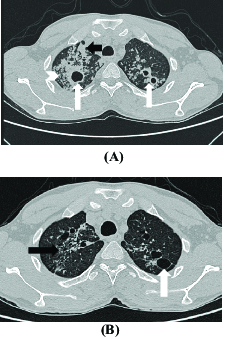

The appearance of a tree in bud is depicted by a pattern of bronchial dilatation and filling on a thin-section chestCT. Tree-in-bud opacities appear as tiny centrilobular branching structures on CT most often in the lung periphery which resemble budding trees Figure 18-4.

However to our knowledge the relative frequencies of the causes have not been evaluated. Recognition of the tree-in-bud pattern. Fairly sharply circumscribed small centrilobular nodules or branching tubular structures 2-4 mm diameter within secondary pulmonary.

Tree-in-bud sign refers to the condition in which small centrilobular nodules less than 10 mm in diameter are associated with centrilobular branching nodular structures 1. My CT scan says defined streaky opacity with associated loss volume and clustered tree in bud nodules have developed in the anterior segment of the upper left lobe. Tree-in-bud pattern seen on high-resolution CT HRCT indicates dilatation of bronchioles and their filling by mucus pus or fluid.

Tree-in-bud sign or pattern describes the CT appearance of multiple areas of centrilobular nodules with a linear branching pattern.